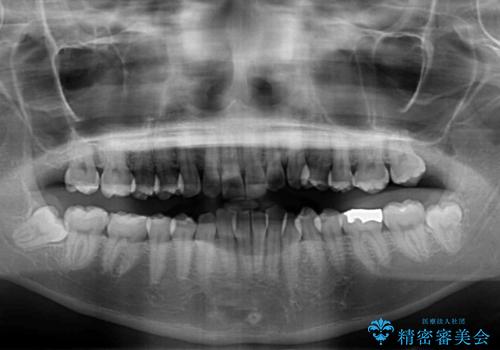

- 上下のクロスバイトと前歯のデコボコを気にして来院された患者様です。

インビザラインを用い、IPR(歯と歯の間を削る)と歯列全体を拡大させることで、歯並びを整えていくこととしました。

下の歯が隠れてしまうほどでしたが、深い咬み合わせも改善され、顎への負担も軽減されました。